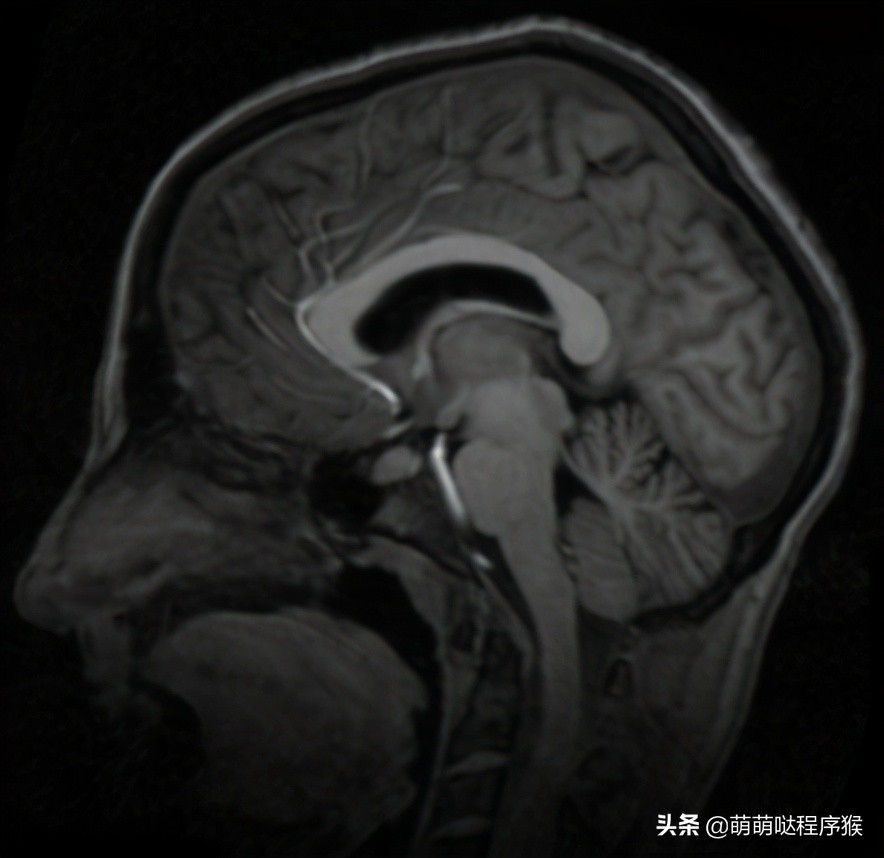

2. 脑部图像配准结果

参考图像

浮动图像

多次迭代过程中浮动图像的变化过程

多次迭代过程中浮动图像与参考图像的差值图变化过程